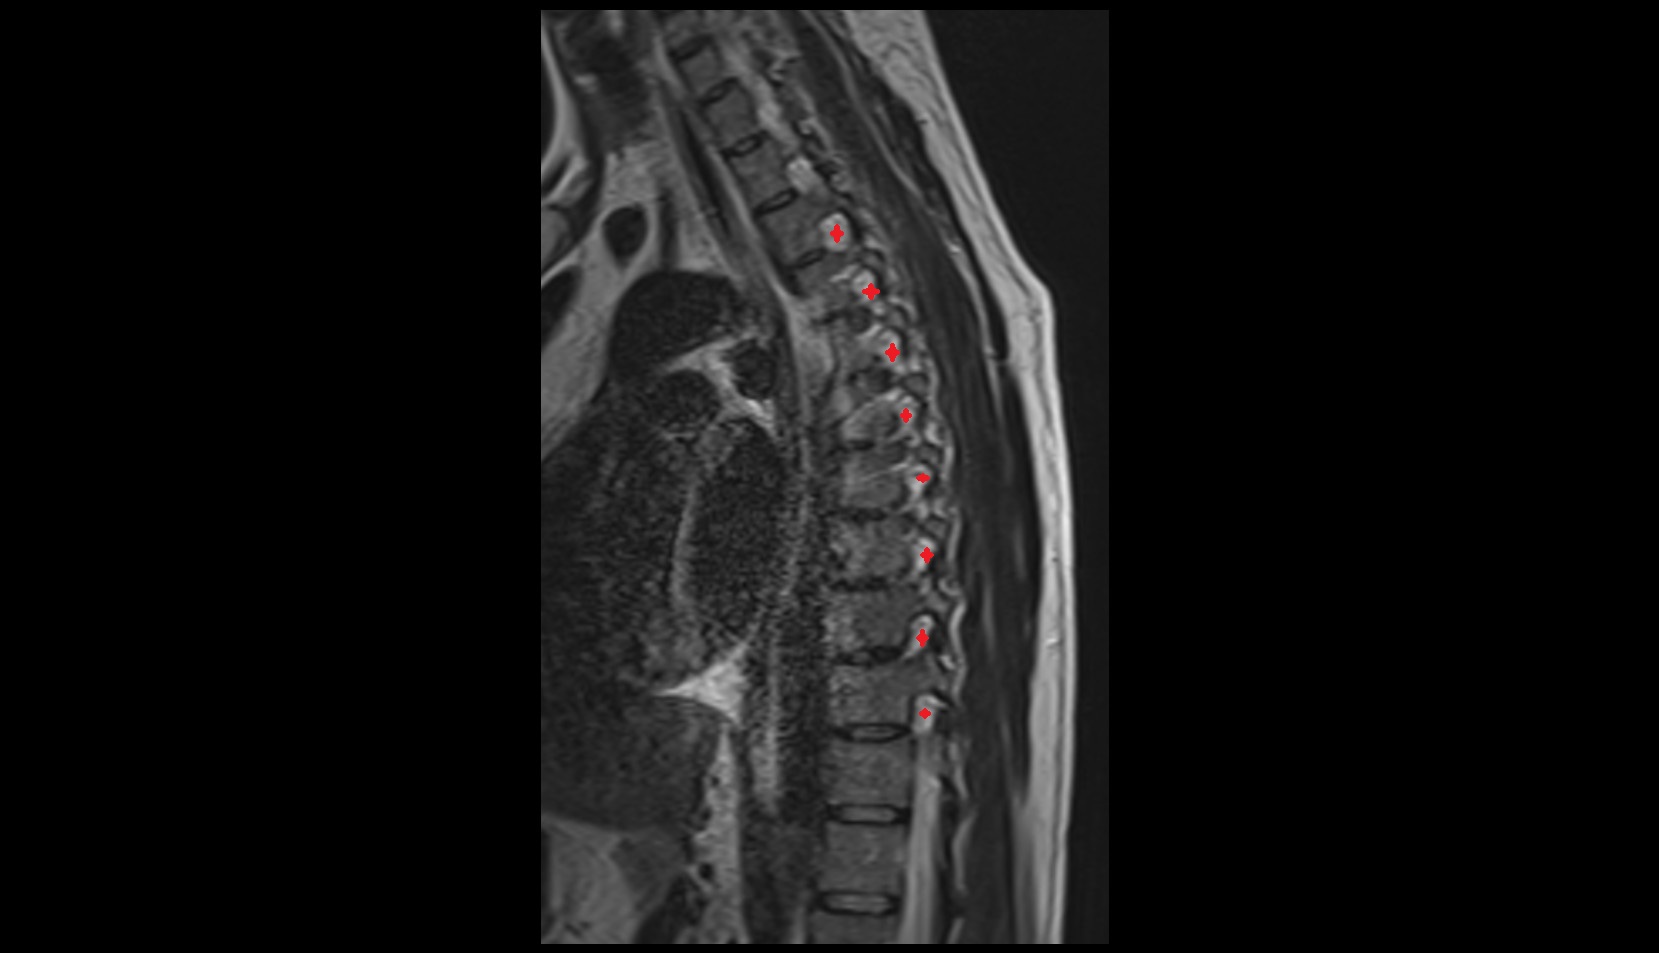

- Spinal dura mater

- Spinal epidural space

- L5–S1 Intervertebral disc

- L4–L5 Intervertebral Disc

- L3–L4 Intervertebral Disc

- L2–L3 Intervertebral Disc

- L1–L2 Intervertebral Disc

- T12–L1 Intervertebral Disc